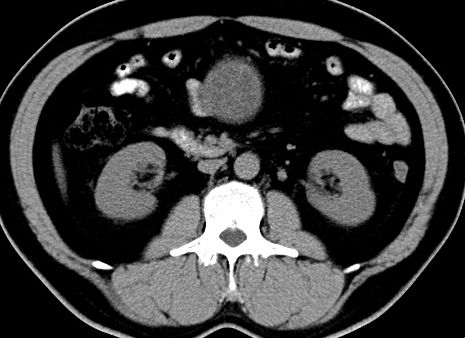

(腹腔)神经鞘瘤

男,48岁,间断性下腹不适1年。

手术探查

:距回盲部28厘米处肠系膜根部可见5*7cm左右包块,质中等硬度,活动度尚可,肝、胆、胰、脾肾未见明显异常。

病理

:(腹腔)

神经鞘瘤

,伴出血、坏死及囊性变,伴淋巴结反应性增生。

免疫组化结果

:sma(-), desmin(-), cd117(-), s-100(+++), nf(-),vimentin(+++).